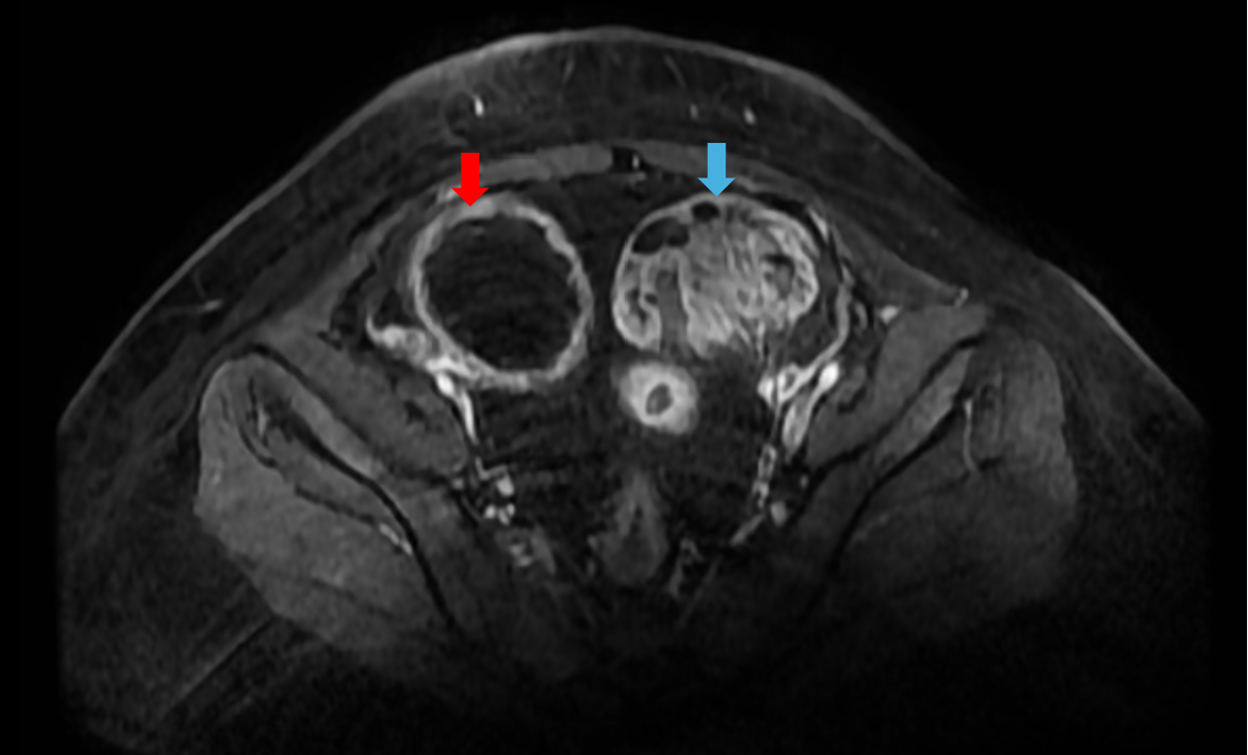

Hình 2: Chụp cộng hưởng từ tiểu khung: Buồng trứng phải: nang lớn kích thước ~73x89mm, dịch bên trong có tín hiệu khá đồng nhất (mũi tên đỏ). Buồng trứng trái: nang lớn kích thước ~74x55mm, có thành phần đặc bên trong kích thước 67x38mm, ngấm thuốc sau tiêm (mũi tên xanh)